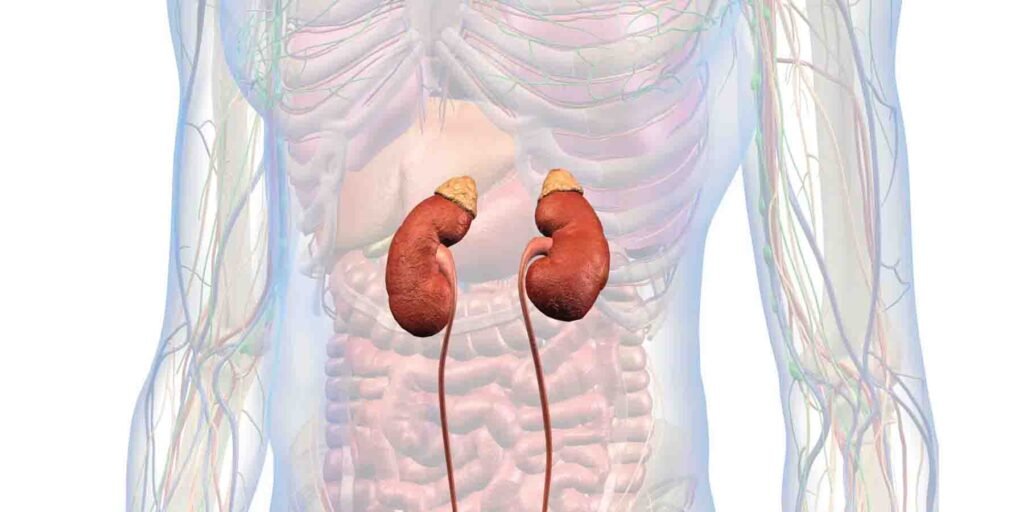

گردوں کے امراض سے بچاؤ کا آسان طریقہ: جدید طبی تحقیق

آسٹریلیا میں ہونے والی ایک نئی تحقیق نے انکشاف کیا ہے کہ مچھلی میں پائے جانے والے اومیگا 3 فیٹی ایسڈز گردوں کے دائمی امراض کا خطرہ 13 فیصد تک کم کر سکتے ہیں۔ ہفتے میں دو بار چربی والی مچھلی کا استعمال گردوں کے افعال کو بہتر بنانے میں کلیدی کردار ادا کرتا ہے۔